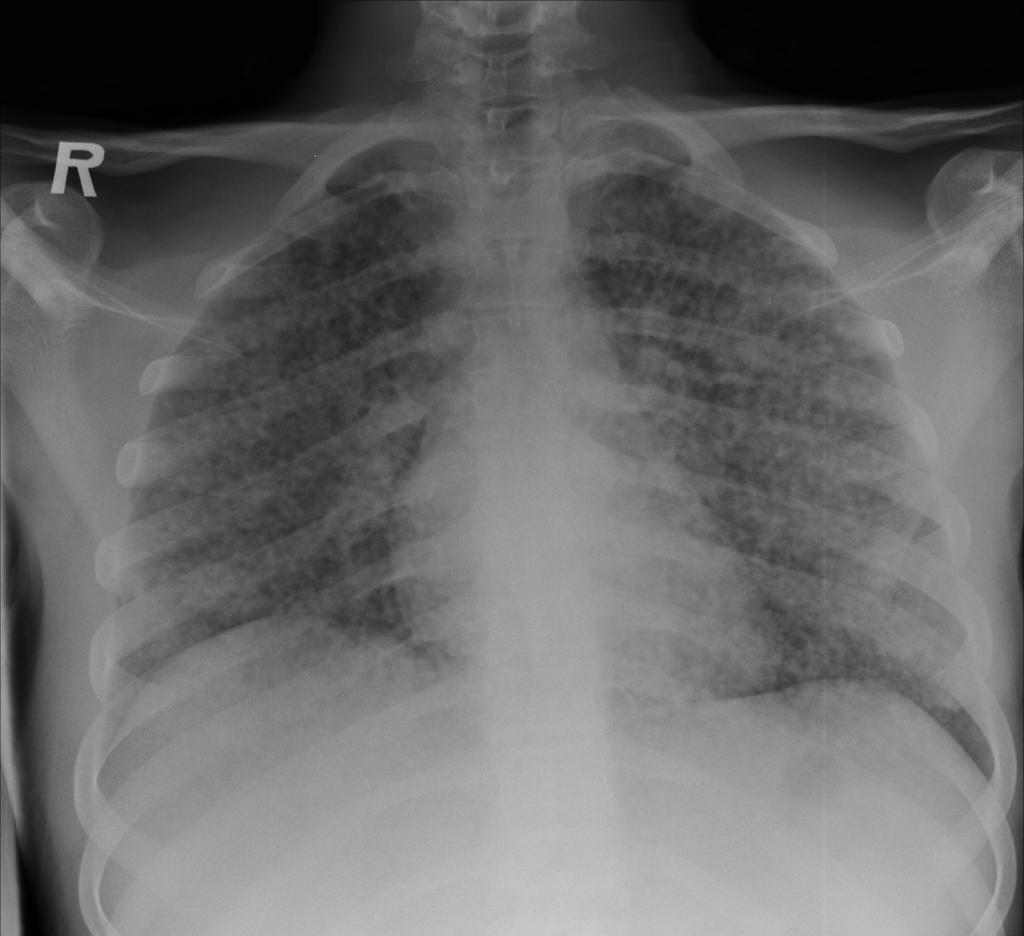

Снимок легких при туберкулезе является важным методом диагностики этого заболевания. На рентгеновских снимках можно увидеть изменения в легких, которые свойственны туберкулезу.

Диссеминированный туберкулез на рентгенограмме

Диссеминированный туберкулез рентген

Диссеминированный туберкулёз лёгких рентген

Фотографии снимков легких при туберкулезе

В данной статье представлены многочисленные фотографии снимков легких при туберкулезе, чтобы помочь вам понять, как выглядят изменения легких на рентгеновских снимках при этом заболевании.